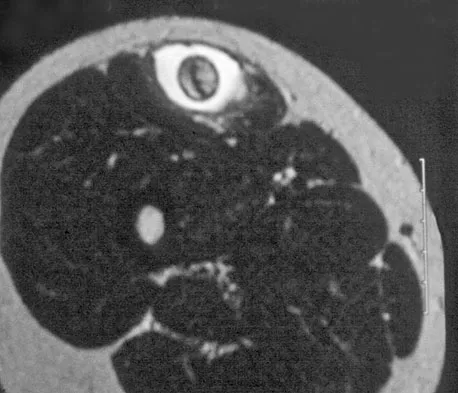

Figure 30 shows an axial cross section of extensor tendon anatomy in zone 7 of the wrist. What letter best depicts the location of the posterior interosseous nerve?